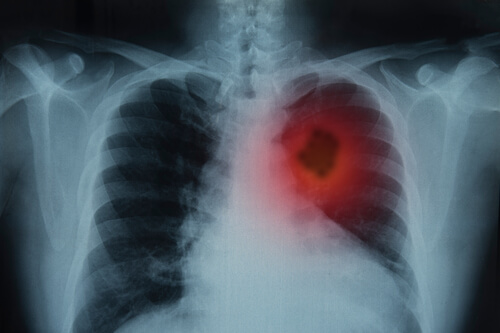

Diagnosi

- Diagnostica per immagini: comprende esami quali Tac, risonanza magnetica, Pet.